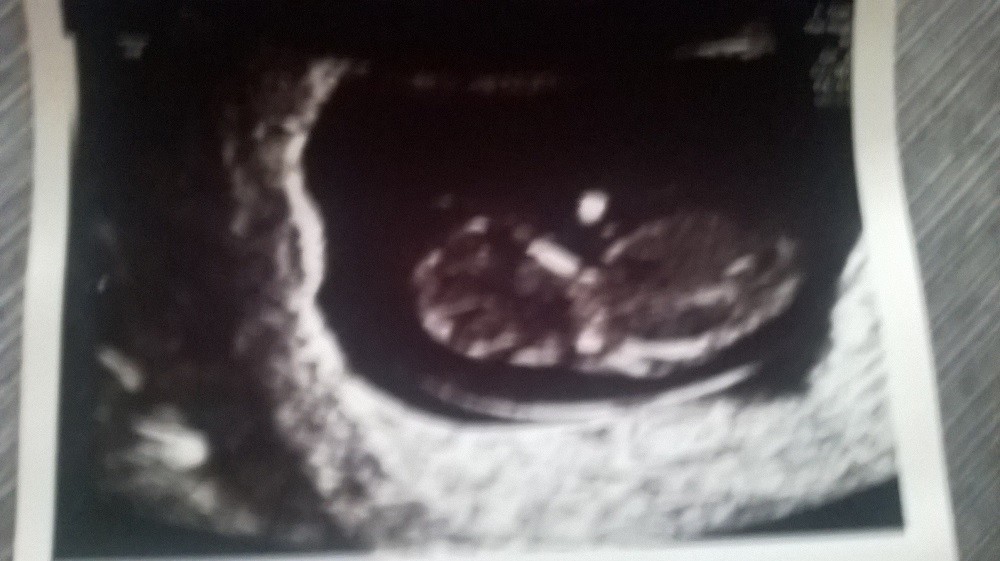

Drugi bobas zdrowy, przezierność idealna, ruchliwy jakby miał ADHD, udzieliły się mu moje nerwy i nie chciał się dać zbadać.

Oto moje niunia...

Zdrowy bobas (czuję, że dziewczynka)

Moje serduszko bijące 140 razy ma aż 1,01 cm :*